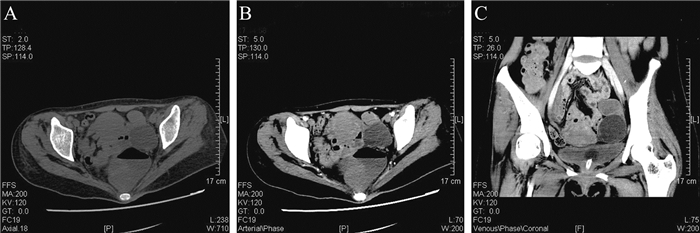

7例患者脑电图异常,主要为背景α节律解体,脑电弥漫性θ/δ波活动(图 1)。6例患者头颅MRI异常,主要累及大脑皮层、小脑、海马、基底节、丘脑、岛叶。病例2患者发病初期于外院就诊,行彩声多普勒超声(彩超) 检查提示左侧卵巢畸胎瘤,已于外院行左侧卵巢畸胎瘤剔除术,后转入我院继续接受治疗;其余8例患者均于我院行盆腔彩超和(或) CT检查,结果均提示附件区包块,考虑畸胎瘤可能性大(图 2)。

图 2 一例抗NMDAR脑炎合并畸胎瘤患者的盆腔CT检查结果 A:横截面平扫;B:横截面增强;C:冠状面增强;该例患者左侧附件区可见一大小约40 mm×37 mm的类圆形包裹性低密度影,壁薄、光滑,其内侧壁可见条状极低密度影;增强扫描囊壁均匀强化,囊内容物无强化 |